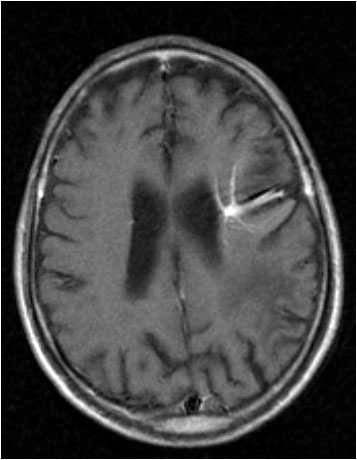

Signo clásico de la angiografía cerebral, también visible en la TC con contraste y en la resonancia magnética, que corresponde a un angioma venoso cerebral o una anomalía venosa congénita.

La imagen está formada por múltiples estructuras vasculares que convergen hacia un punto en el parénquima cerebral. En la TC con contraste se ven como líneas densas. En la RM la intensidad de señal puede ser variable en función de la secuencia. En la imagen se ven líneas hiperintensas en una secuencia T1 con gadolinio.

El nombre del signo, Medusa, hace referencia a un monstruo de la mitología griega que se representa como una cabeza con serpientes.